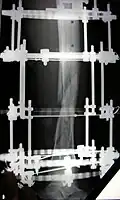

The photographs and radiographs illustrate the application and emplacement of an external fixator, an Ilizarov apparatus, to repair the open fracture of the lower left leg of a man. The photographs were taken four weeks after the patient fractured the shinbone (tibia) and the calfbone (fibula) of his left leg, and two weeks after the surgical emplacement of the Ilizarov apparatus to immobilise the leg and isolate the wound and fracture site to facilitate healing.

X-ray of the open fracture site immediately after installation of the Ilizarov apparatus.